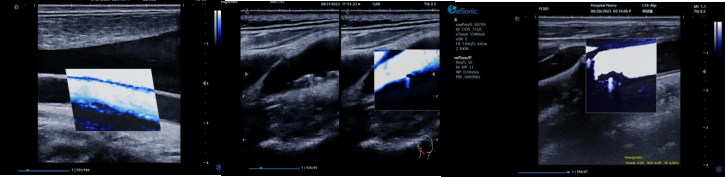

QPWV 彩色脉搏波传导速度定量技术

QPWV 技术是新航娱乐医疗的极速脉搏波速度测量技术,对脑卒中诊疗优势明显:

image.png

? 可进行动脉壁运动速度 - 时间彩色成像,直接测量单点脉搏波传导速度及相关参数(如 BSES 时的速度及标准差)。

? 能在血管内中膜增厚前的内皮功能不全阶段检测异常,对早期动脉硬化评估极具临床价值。

? 操作简单直接,无需附加设备,影响因素少,检测快速、重复性和稳定性高。